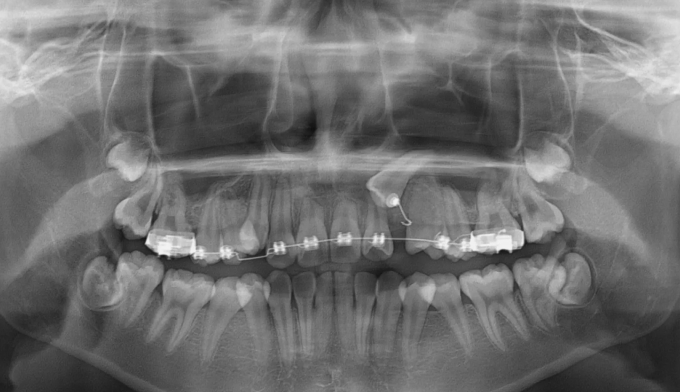

매복치의 방향이 수평으로 누워있기 때문에 저절로 구강내로 맹출하지는 못합니다.

따라서 잇몸 절개 후 교정장치를 부착하여 치아를 견인해주어야 합니다.

총 치료기간은 17개월 소요되었습니다.